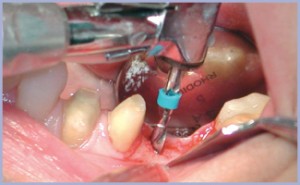

Dopo avere allestito il lembo a spessore totale (figg. 2, 3), si preparano due alveoli chirurgici, uno per l’impianto che sostituirà la radice mesiale, orientato in modo tale da risultare in asse con i carichi funzionali che si creano nella fase di entrata del ciclo masticatorio ed uno che sostituirà la radice distale, orientato in asse con i carichi funzionali che si creano nella fase di uscita. Poiché è necessario intaccare la corticale con estrema precisione, si inizia la preparazione con una fresa a palla montata su turbina (figg. 4, 5); si prosegue con il protocollo classico (figg. 6-14). Si inseriscono gli impianti, si assemblano i relativi tappi (figg. 15-19) e si sutura (fig. 20) secondo il protocollo bifase. Dopo tre mesi, quando l’osteointegrazione ha raggiunto una maturazione sufficiente ad assicurare la stabilità primaria degli impianti, si interviene con il secondo momento chirurgico per posizionare i tappi di guarigione e creare i condotti mucosi (figg. 21-24) che si epitelizzeranno in circa dieci giorni. Segue la presa delle impronte mediante transfer da impronta (figg. 25-28). Il tecnico assembla gli analoghi da gesso sui transfer, sviluppa i modelli, monta i monconi sugli analoghi ed esegue il fresaggio (fig. 29). In studio si verificano i monconi (fig. 30) e si rimandano in laboratorio per la preparazione delle cappette (fig. 31) e la relativa ceramizzazione (fig. 32).

- Fig. 4

- Fig. 5